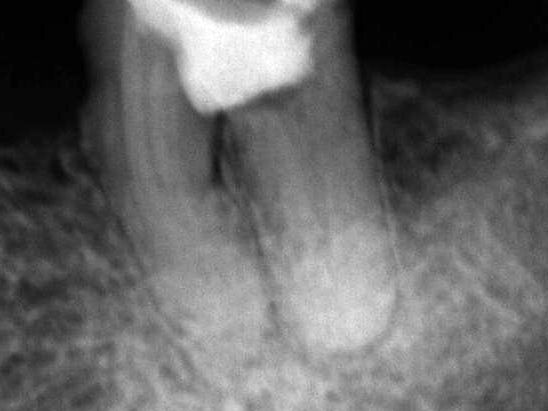

Paciente do gênero feminino, 47 anos, apresentou-se com quadro clínico de extensa perfuração iatrogênica da região de furca do elemento dental 36 (figuras 1 e 2), associado à perda óssea radiograficamente, fístula vestibular e dor à palpação.

A obturação foi realizada pela técnica termomecânica Híbrida de Tagger (figura 3), por meio do emprego de GutaCondensor (Maillefer/Suiça), cones de guta-percha TP (Dentsply/Brasil) e cimento obturador à base de M.T.A. Fillapex (Angelus/Brasil).